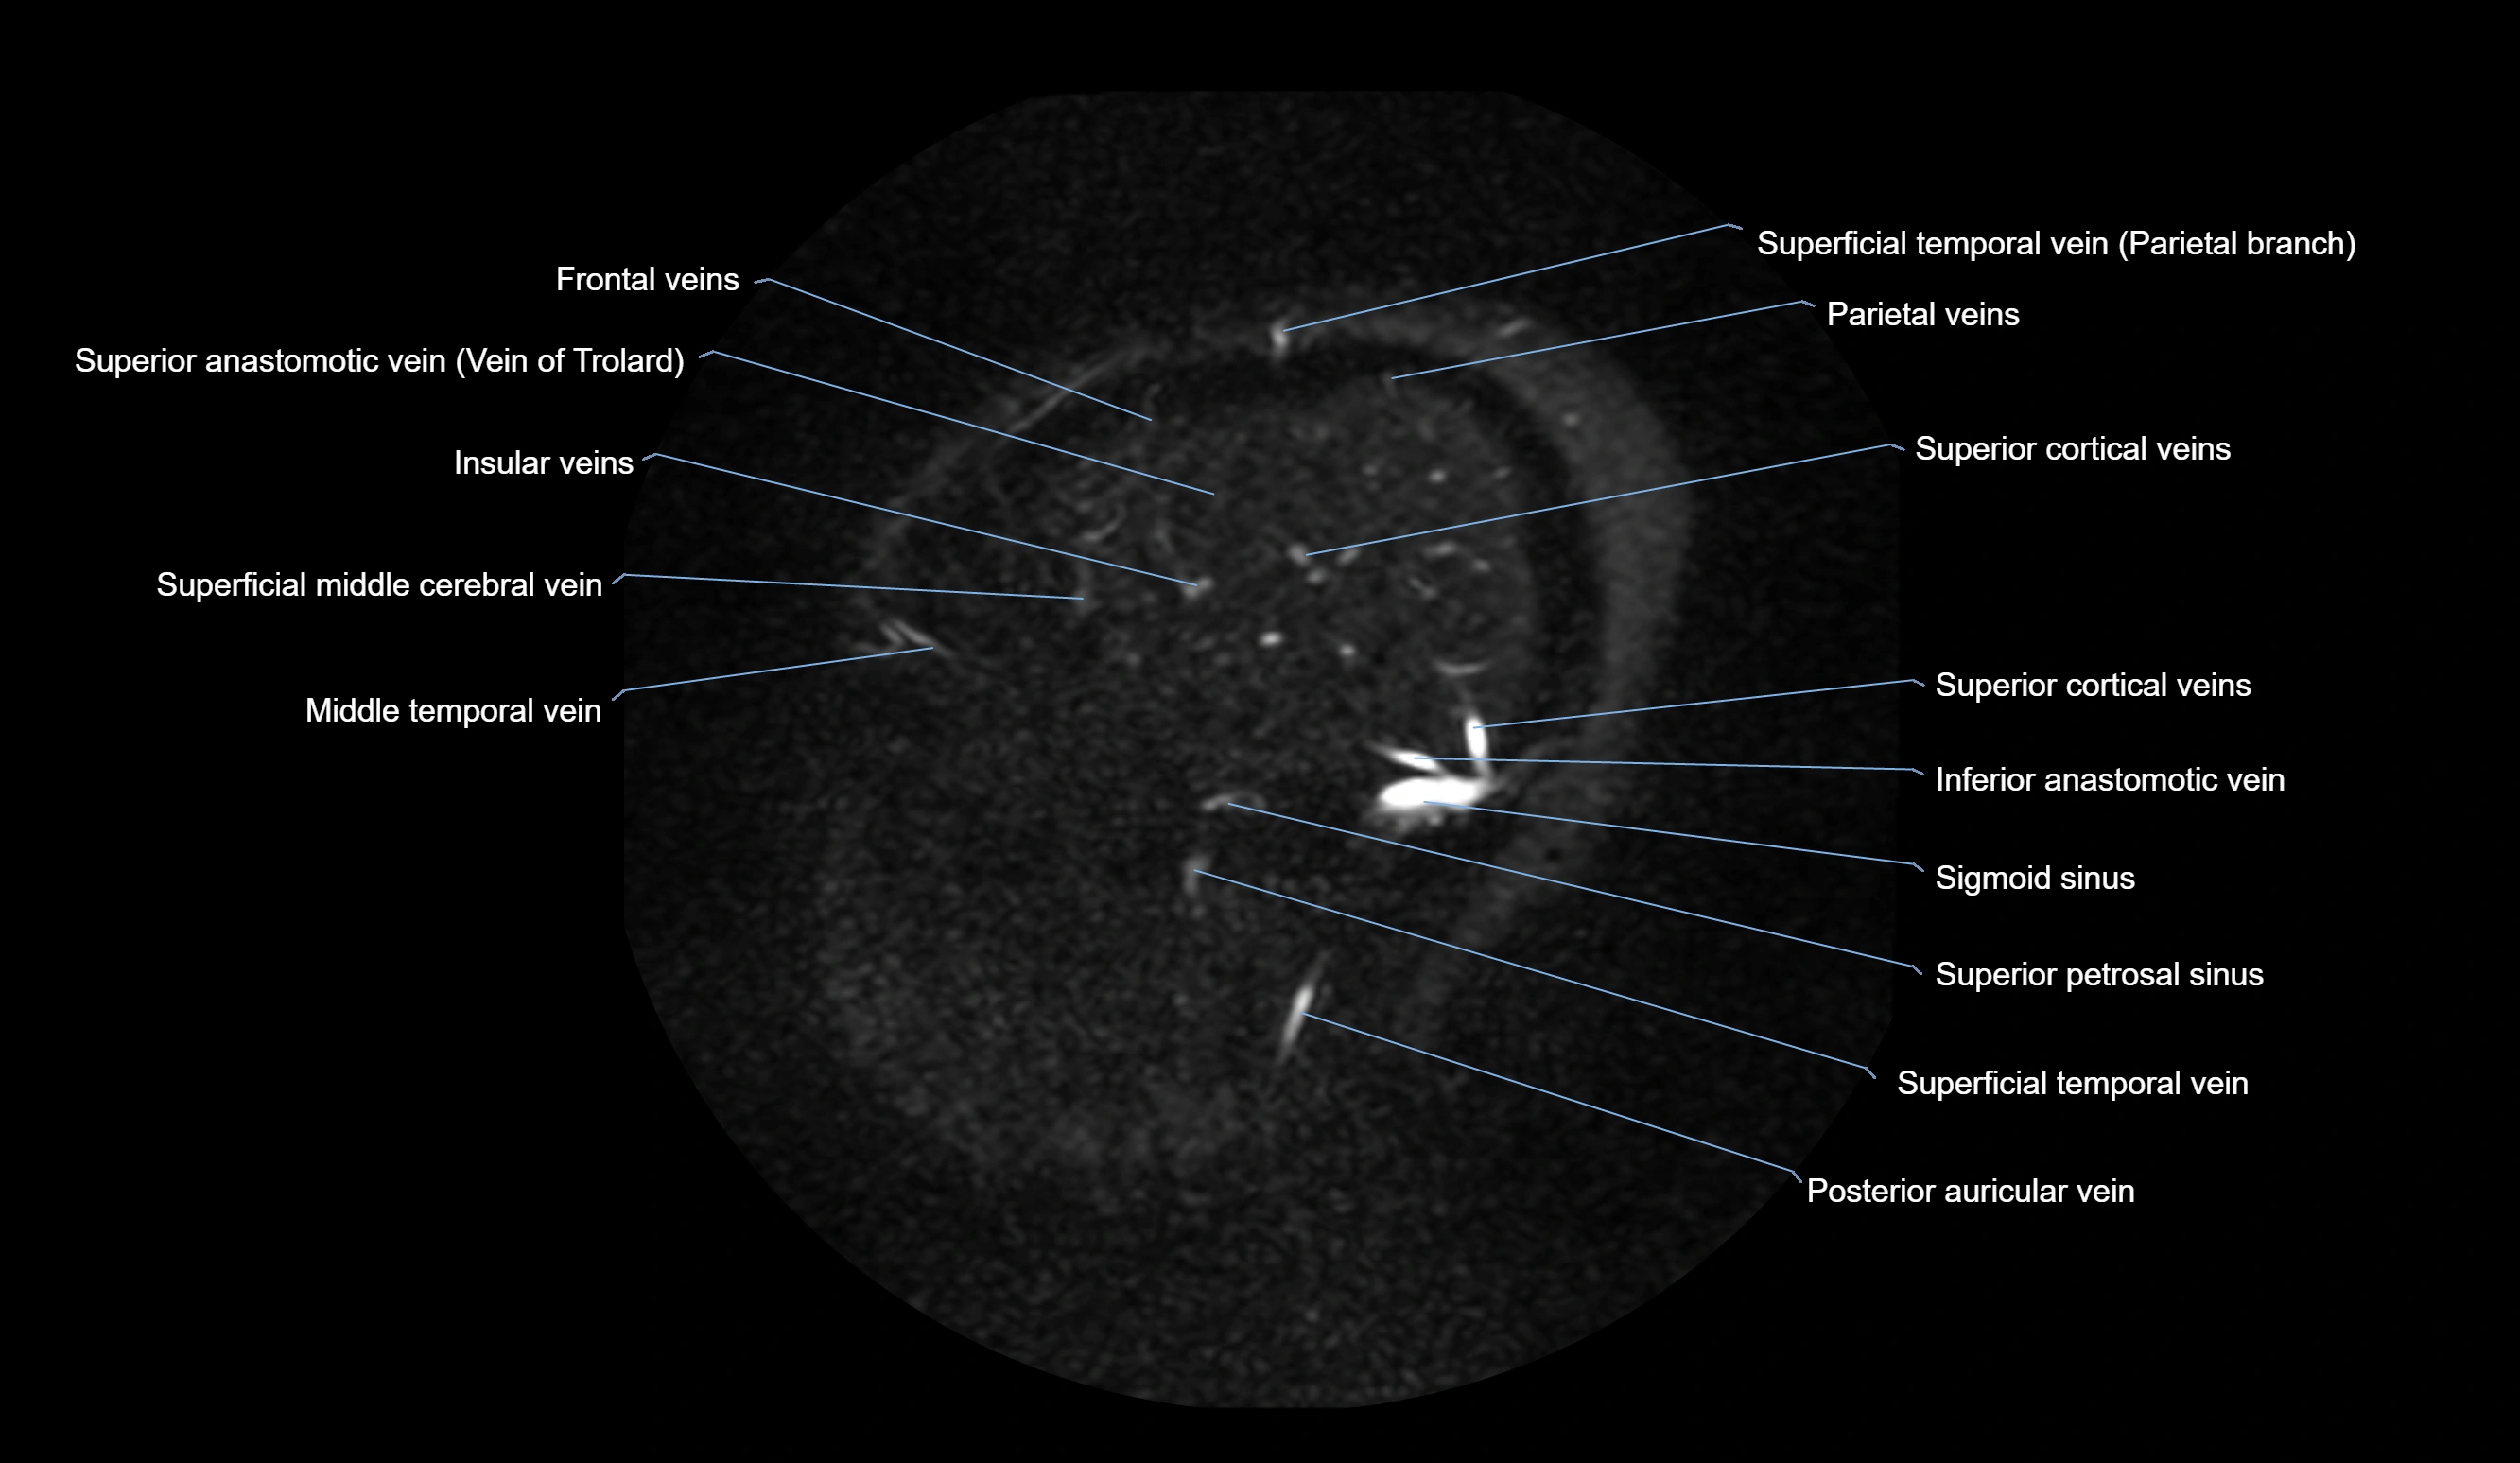

MRI images

image